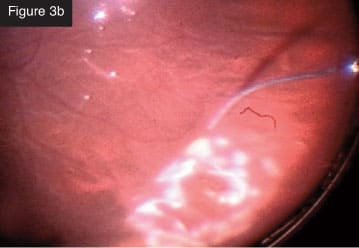

Membrane removal with vitrector. CASE 3: Total rhegmatogenous retinal detachment. I frequently combine scleral buckling with small-gauge vitrectomy. In a recent case of total rhegmatogenous retinal detachment (Figures 3a and 3b), I first did the scleral buckle and then removed the vitreous from the periphery with minimal traction on the retina. The creation of iatrogenic breaks is markedly reduced with this technology. I injected perfluorocarbon liquid and aspirated subretinal fluid. I like to aspirate often with the vitrectomy probe through the break. Next, I applied laser photocoagulation to the break. With the flexible tip laser probe, I find I can treat that entire area in an elegant, quick way, even in phakic

Rhegmatogenous retinal detachment.

Bidirectional laser to breaks. CASE 4: Tractional detachment in silicone-filled eye. Silicone oil removal and injection can be done beautifully through small gauge with the CONSTELLATION® System. In this case, I entered through the limbus to remove droplets of emulsified silicone oil from the anterior chamber (Figure 4a). Then, I used forceps to lift the membrane that was causing the tractional detachment (Figure 4b). After lifting off the membrane, I was able to remove everything with the cutter (Figure 4c). I still utilize forceps in some cases, but I use them less often with this technology.